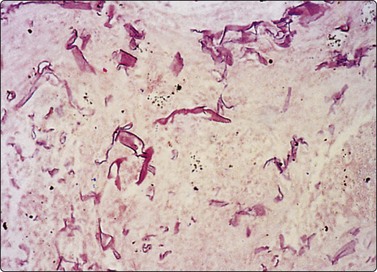

image image

Fig. 8.6 Caseation necrosis

(A) Amorphous and granular debris with neutrophils (H&E, MP); (B) Single-cell pattern of necrosis (H & E, HP).

Fig. 8.7 Mycobacterial infection

(A) Negative images of bacilli in a background of granular necrotic debris (MGG, HP); (B) Numerous acid-fast bacilli, including clumps of beaded forms (Ziehl-Neelsen, HP; Inset HP oil).

Epithelioid histiocytes are fairly cohesive and form granulomas which are often aspirated intact (Fig. 8.5). Epithelioid cells have an elongated or bean-shaped nucleus and abundant cytoplasm which is rather pale and indistinct both in Pap- and H & E-stained specimens (Fig. 8.5). The cytoplasmic density is higher in MGG-stained material. Multinucleated histiocytes can be seen but are usually sparse. They are mainly free of intracytoplasmic pigment or birefringent material, unlike the multinucleated histiocytes seen in non-specific reactions in pulmonary tissue. Caseous necrosis has a variable appearance. There may be an amorphous to granular background with little cell outline visible, but sometimes outlines of necrotic cells may be prominent (Fig. 8.6) and often the appearances are merely of nondescript debris, histiocytes and neutrophils. Dahlgren cites granular calcific material as a common accompaniment.98 Lymphocytes may be plentiful in granulomatous inflammation.

Bailey et al.99 diagnosed 28 of 34 cases of TB by either auramine rhodamine fluorescence or positive culture; acid-fast bacilli (AFB) were seen in only 38% of cases. In Rajwanshi’s102 and Das’s103 series AFB were identified in approximately half of the cases. Gong et al. found PCR to be about 80% sensitive compared to 40% for ZN staining in FNB material.171

Acid-fast bacilli are more often seen in cytological material characterized by a mixture of neutrophils, histiocytes, mucoid or necrotic material than in those lesions with a prominent epithelioid cell component,99,102 though culture is positive in a similar percentage of cases with and without epithelioid cells.103 Whenever necrotic debris is seen, we restain smears with ZN stains. Maygarden described mycobacteria as negative images in a stained background in MGG material (Fig. 8.7).182 Silverman reported negative images in both Diff-Quik and Papanicolaou-stained material in a BAL sample from a patient receiving clofazimine treatment for an atypical mycobacterial infection. The reddish, refractile and polarizable drug-derived crystals can impart a pseudo-Gaucher-like appearance to the cells, simulating the negative images of an atypical mycobacterial infection.183